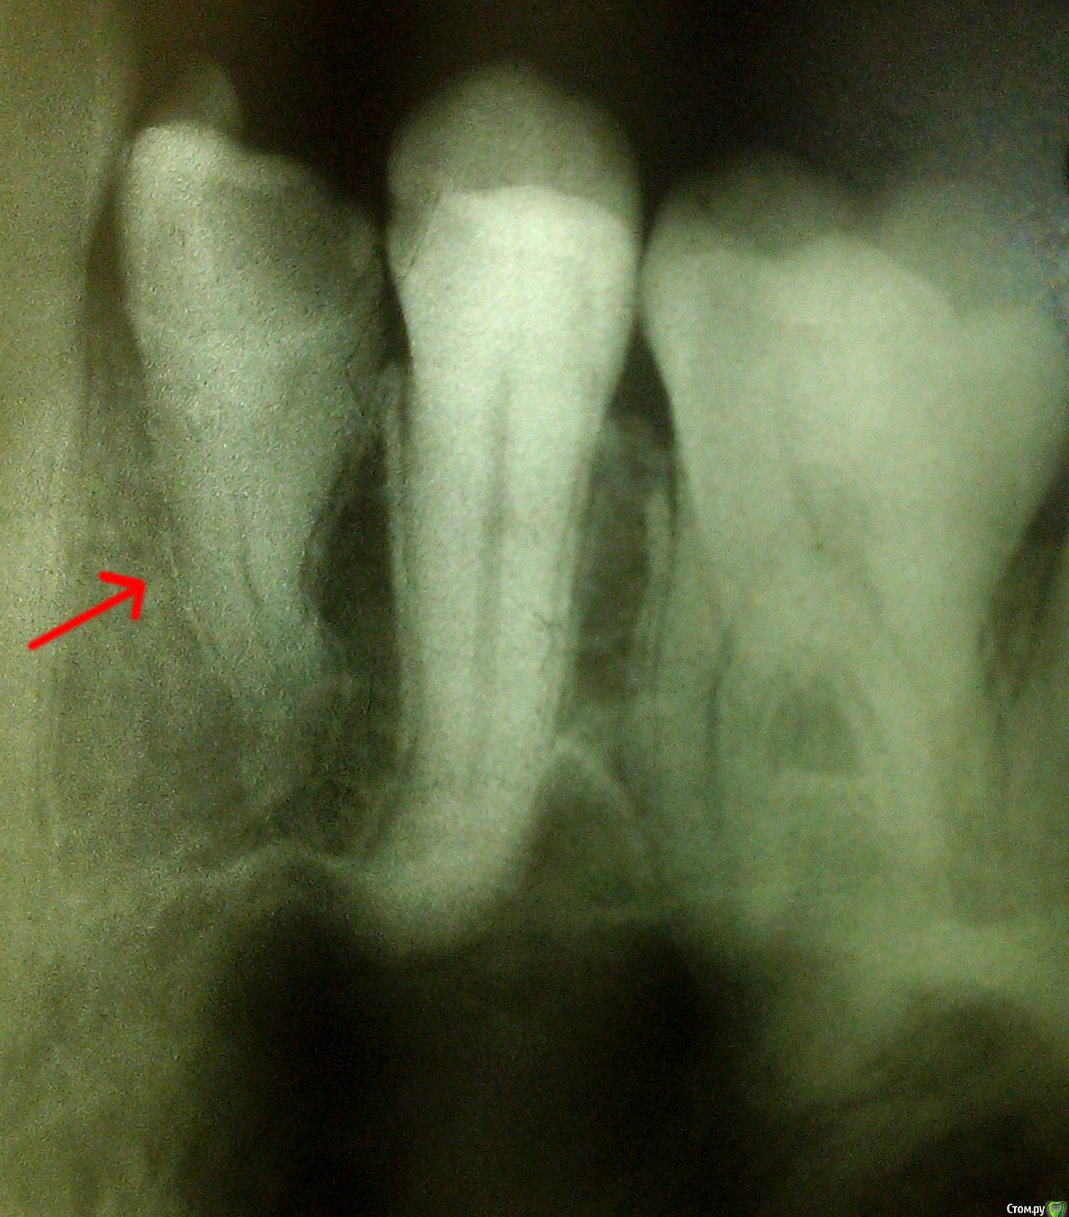

Swift44 Опубликовано 13 ноября, 2016 Поделиться Опубликовано 13 ноября, 2016 Здравствуйте, уважаемые доктора!Прошу вашего совета. Обратился в государственную поликлинику.Скололся зуб 1.4.Доктор не может найти каналы и хочет заложить резорцин-формалиновую пасту в полость зуба и запломбировать его, не обрабатывая каналы, т.к. считает, что высок риск перфорации корня. -----Ход лечения. Первый визит.Была попытка найти канал по болевым ощущениям (без анестезии).Болевые ощущения были, но каналы найти не удалось.Был заложен депульпин. Второй визит.Доктор хотел заложить резорцин-формалинувую пасту, но я настоятельно попросил избежать ее использования. Канал найти не удалось. В полость зуба помещена паста-расширитель на 4 дня.----- 1. Правильно ли я понимаю, что резорцин-формалиновый метод лечения совершенно неприемлем: при использовании метода ткани зуба будут временно законсервированы, затем через некоторый промежуток времени воспаление возобновится, и зуб придется перелечивать, но уже к проблеме поиска каналов присоединится проблема удаления полимеризованной пасты?2. Могут ли появиться еще какие-либо проблемы из-за такого лечения? Ссылка на комментарий